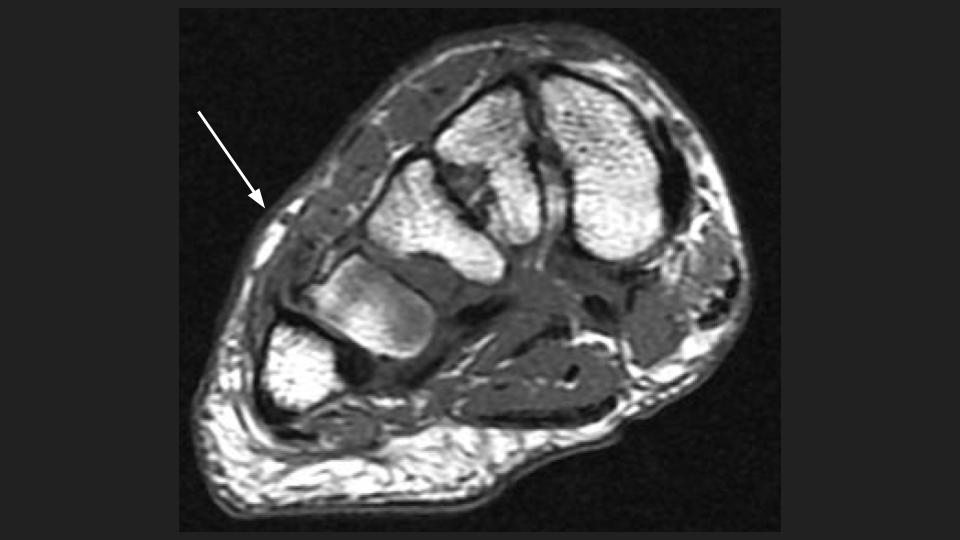

Figure 2 for case peroneus tertius ( RID2915 )

Figure 2

Area of pain indicated by markers surrounds the insertion of the Peroneus Tertius tendon onto the base of the 5th and likely also 4th dorsal MT base. The tendon is thickened with intrasubstance intermediate T1 and bright T1 signal. This is the insertional tendinosis of the peroneus tertius, with probable superimposed partial intrasubstance insertional tear suggested in the Sag fat sat images. The reference does not say much about the insertion, but includes some anatomic references that indicate variation in the insertion site at the 5th and sometimes 4th and 5th MT base. Reference article.